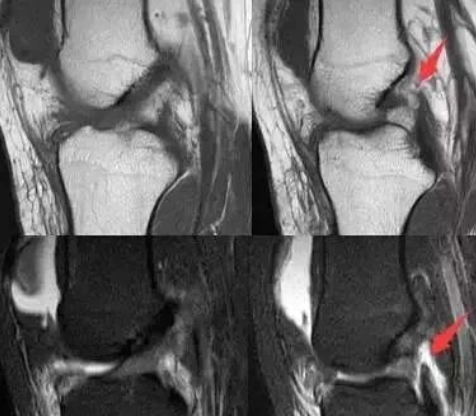

2023年欧放教育展板:半月板撕裂概念更新!